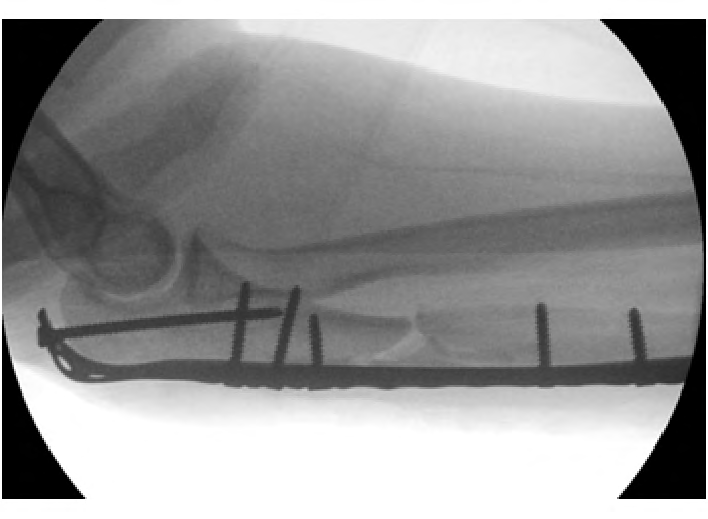

右前臂术中透视影像显示尺骨骨折接近解剖复位,桥接钢板固定,桡骨头复位

伤后第7天,骨科与神经外科医师联合查房,对患者全身情况进行评估,讨论进一步处理意见,会诊后同意适时对右侧孟氏骨折及肱骨干骨折实施手术治疗。遂于股骨髓内钉固定术后第6天对右侧尺骨骨折进行切开复位,恢复尺骨长度,桡骨头自然复位,尺骨用钢板螺钉进行桥接固定,透视证实复位良好。术后患者神经外科情况逐渐好转并出院。